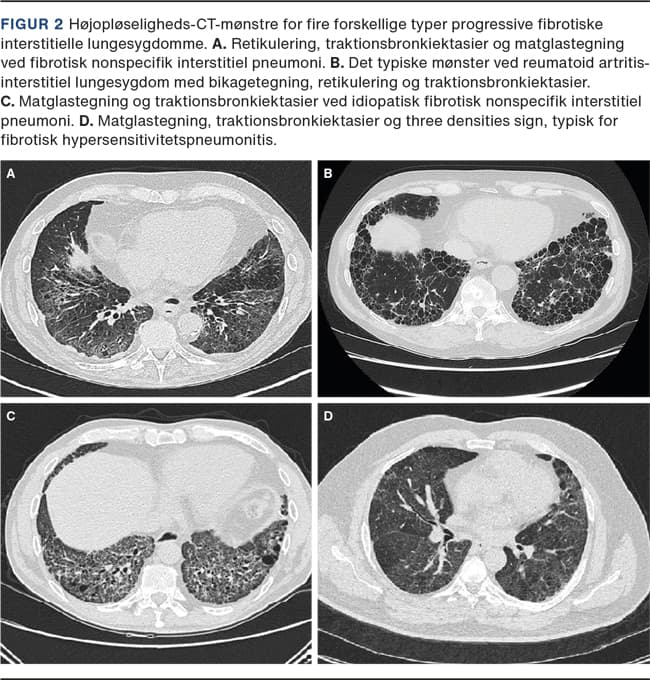

Med HRCT kan man bekræfte ILS med fund af f.eks. subpleural retikulering, bikagetegning, traktionsbronkiektasier, matglastegning, noduli, cyster eller konsolidering. Skanning i både in- og eksspiration kan afsløre bestemte mønstre, der er kendetegnende for de forskellige PF-ILS-typer, f.eks. air trapping ved fHP [1]. Figur 2viser HRCT-snit af fire forskellige PF-ILS-typer.

BAL med differentialtælling af leukocytter foretages ofte, f.eks. kan fund af lymfocytose indikere HP, iNSIP og sarkoidose. Ved evt. transbronkial kryobiopsi eller kirurgisk lungebiopsi udtages lungevæv til mikroskopi mhp. vurdering af histologisk arkitektur. BAL suppleres med biopsi fra bronkial mucosa og lymfeknuder, når der er mistanke om sarkoidose.